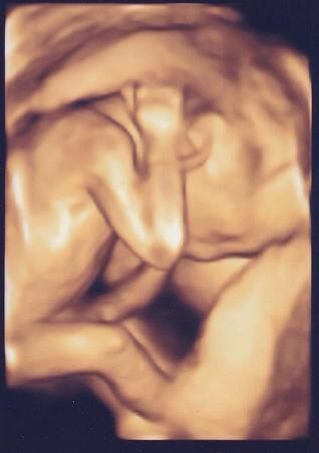

ポコポコさんは動きが激しく、気持ち悪いくらいです、笑。

皮膚が飛び出ると、ビビります。

生きているのねー。

頭を抱えて、悩みでもあるのかな。

生きていくって、大変よね、笑。

もう20cmくらいあるみたい。

順調で、ありがたい限り。